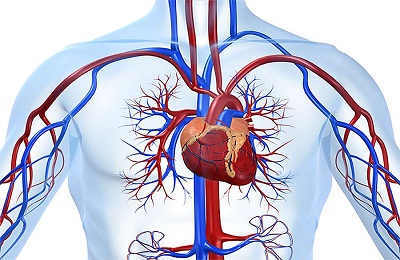

A fő feladata az emberi test vérerek -, hogy biztosítsák a teljes közlekedési vér szervekben és szövetekben.

Ehhez a test egy nagyon jól kidolgozott artériás és vénás hálózat, amely behatol minden szöveteket és szerveket. Ha problémák vannak ezzel a mechanizmussal, vannak bizonyos tünetek emberben.